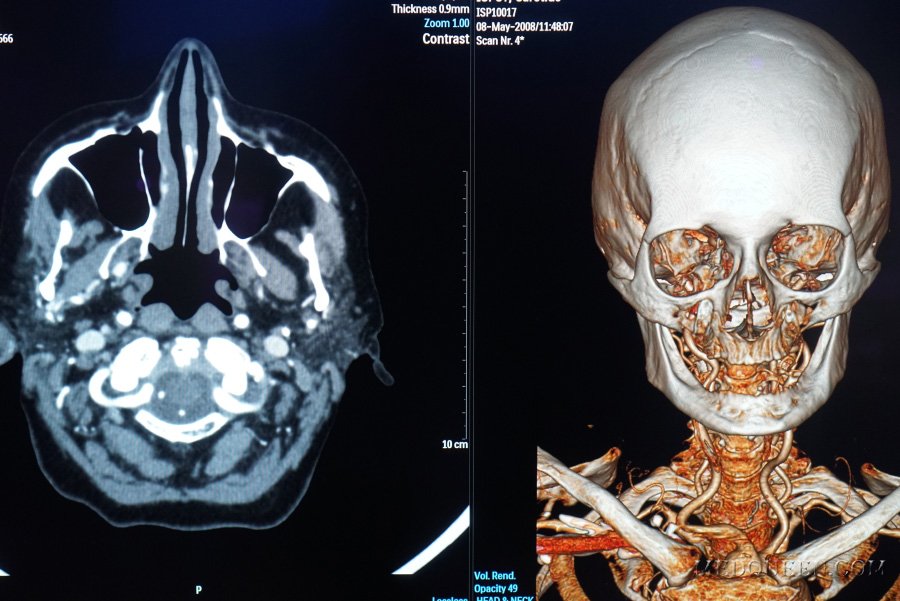

Двигательные и периферические чувствительные волокна пролегают через мост и идут к полулунному узлу Гассера (узел Гассера находится на передней поверхности пирамиды височной кости) (рисунок 8). Отсюда nervus ophthalmicus (глазная ветвь) через верхнюю глазную ветвь идет в глазницу, а nervus mandibularis (нижнечелюстная ветвь) и nervus maxillaris (верхнечелюстная ветвь) через овальное и круглое отверстия выходят из полости черепа (рисунок 9).